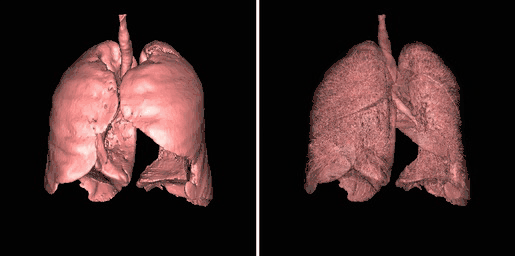

A second example of using an opacity table is shown in the following figure. Here, axial CT data from the patient's airways have been segmented using a region growth technique and the result processed using surface rendering, with full opacity as shown in the left panel and with a reduced opacity (30%) as shown in the right panel:

Notice that internal features of each lung can be discerned when the opacity is reduced. Notice also that continued viewing of this type of transparency display can generate apparent reversal of the image rotation, similar to that noted for the 3D MIPs above. One method of overcoming this type of problem is to segment each lung, for instance. and to blend the results, as illustrated in the following figure:

subFusion Processing